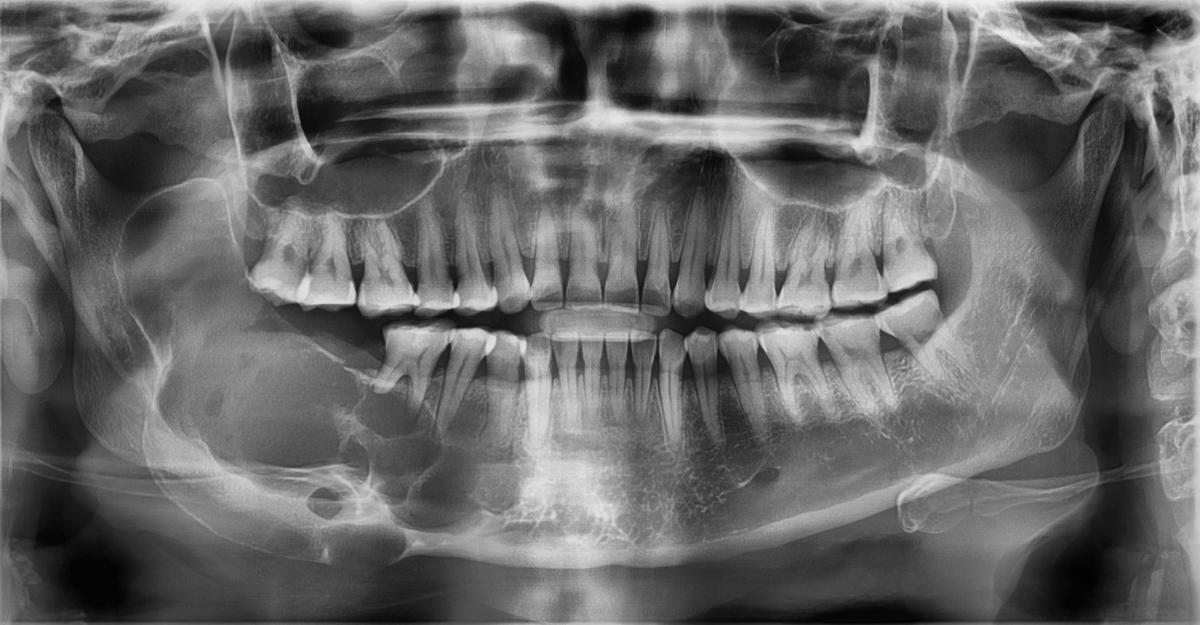

L'examen clinique et radiographique

Lors de l’examen clinique, le médecin examinera attentivement la zone affectée pour déterminer si elle est enflée ou sensible au toucher. Il peut également prescrire une radiographie panoramique pour obtenir une vue complète du crâne et de la mâchoire afin de confirmer le diagnostic.